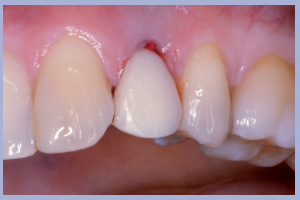

- Fig. 1 – Agenesia dei laterali superiori con mesio-dislocazione dei canini permanenti al posto degli incisivi laterali. Visione frontale

- Figg. 2a, b – Visioni laterali dei canini decidui

Nel presente caso clinico si tratta della sostituzione implanto-protesica di due incisivi laterali superiori agenesici in una Paziente di sesso femminile. L’agenesia degli incisivi laterali era associata a mesio-dislocazione dei canini al posto degli incisivi laterali e dunque l’obiettivo terapeutico era rappresentato dalla sostituzione dei denti mancanti in zona canina e dalla trasformazione protesica dei canini permanenti presenti in incisivi laterali.

L’esame clinico iniziale (Figg. 1, 2) metteva in evidenza una buona situazione dento-parodontale generale; l’igiene orale e la collaborazione da parte della paziente, fortemente motivata alla soluzione del problema, erano ottime. L’esame radiologico ortopanoramico iniziale (Fig. 3) mostrava una buona quantità di osso apicalmente alle radici degli elementi decidui che apparivano sottili e parzialmente riassorbite. Il progetto terapeutico prevedeva un posizionamento implantare post-estrattivo immediato associato a carico immediato non funzionale tramite l’utilizzo di monconi temporanei e corone in resina precedentemente allestite, da ribasare in bocca dopo la preparazione dei monconi.